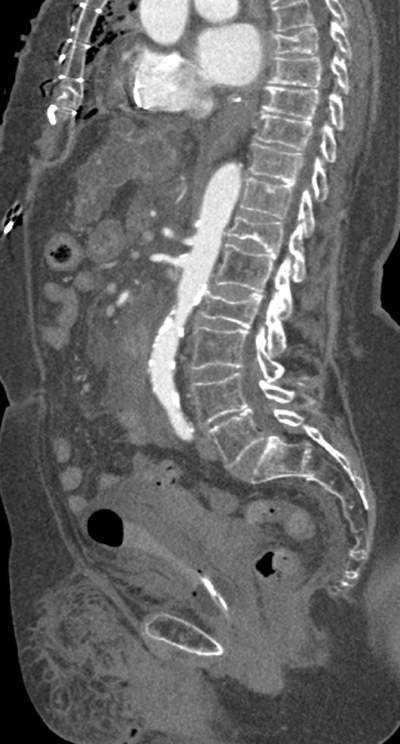

CTA demonstrated good opacification of the thoracic aorta up to the level of the superior mesenteric artery (SMA). However, more distally, no marked enhancement of the aorta and visceral vessels was obtained (Figures 3–5).

Figure 4

Parasagittal reformatted image of the watershed zone (black arrows) at the level of the superior mesenteric artery (SMA).

In this case, no luminal contrast opacification nor active haemorrhage distal to the SMA was present due to the watershed phenomenon, with the blurred area at the level of the SMA and despite the haemorrhage surrounding the right superficial femoral artery.

Since distal to the SMA no vascular enhancement was obtainable, active bleeding could not be ruled out. Awareness of the watershed phenomenon is crucial, since artefacts can be mistaken for pseudolesions such as thrombus, dissection, or vascular occlusion. The watershed area can also potentially obscure true pathology [2], with potentially fatal consequences, as in this case where an active bleeding could be overlooked.